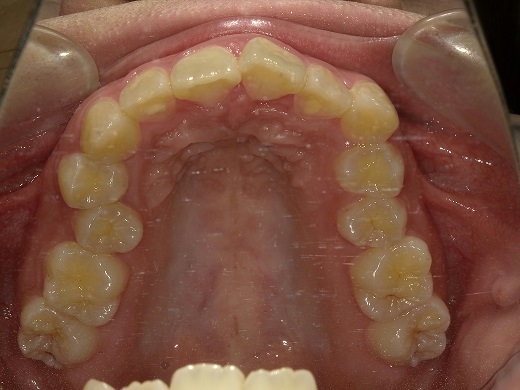

治療後上顎

治療後下顎